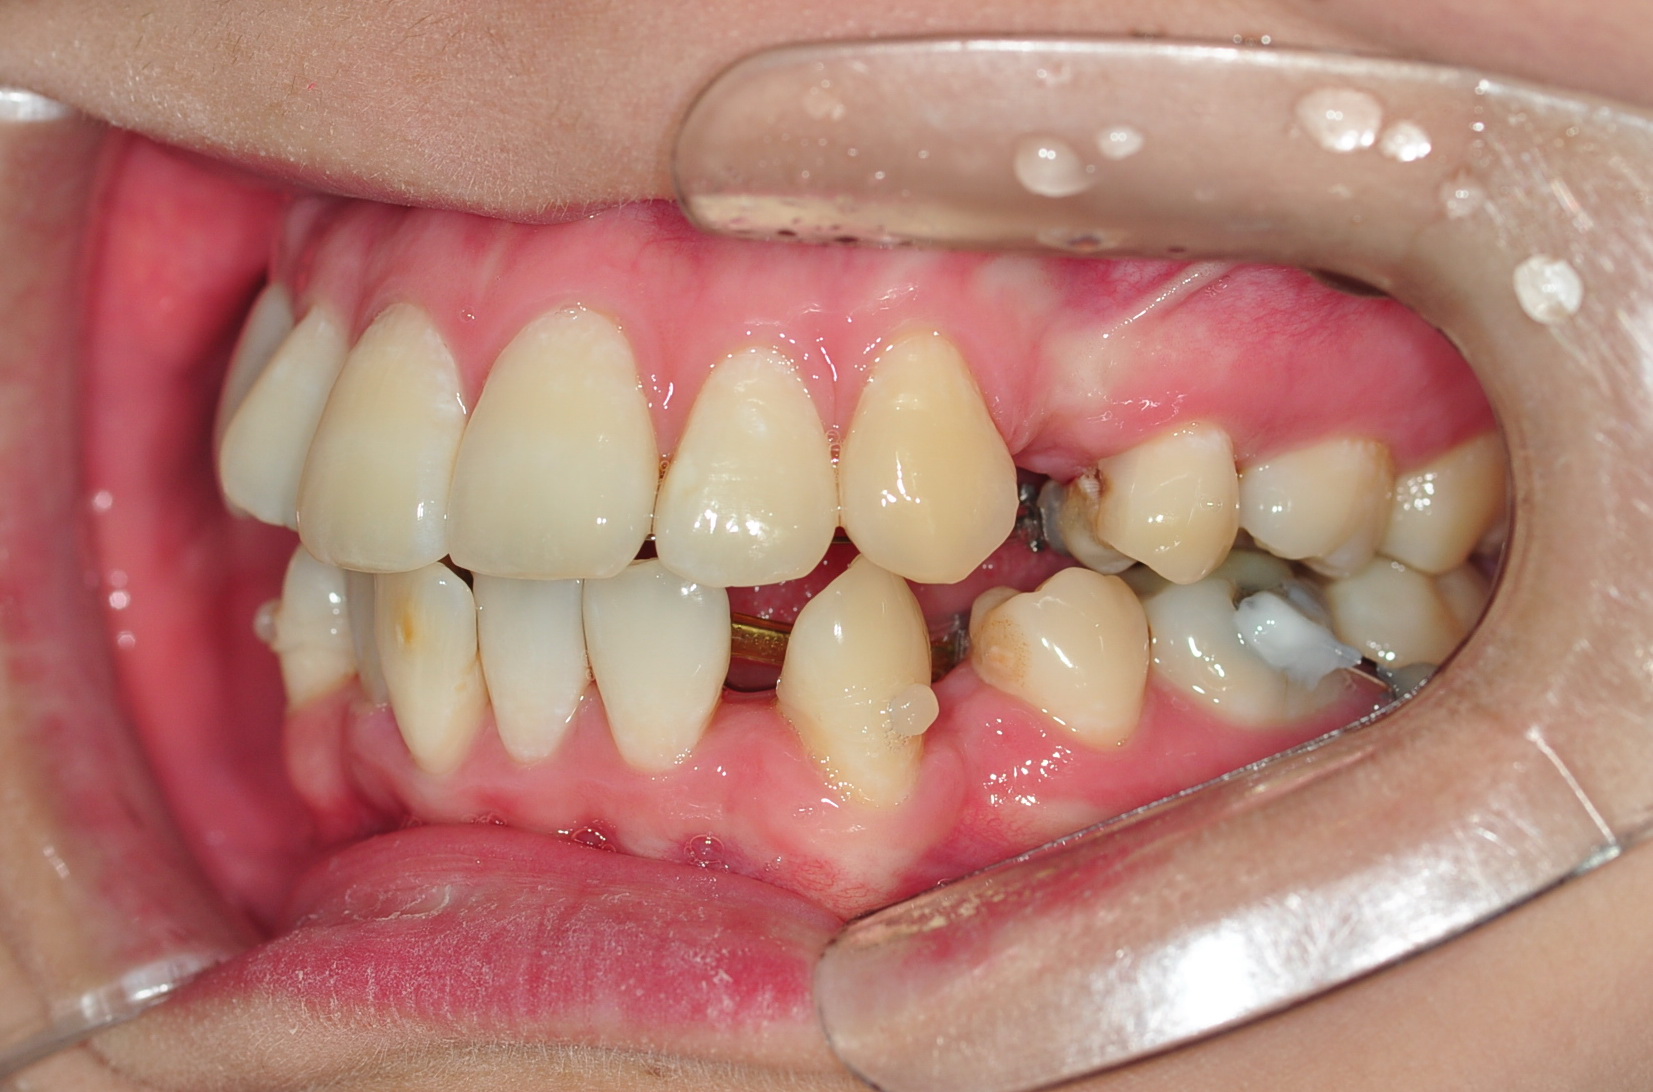

그런데 복병이 생겼어요 ….. ㅠ.ㅠ 미처 발견되지 못했던 충치가..

치아교정치료를 하면서 치아사이가 벌어지면서 발견되었답니다. ㅠㅠㅠㅠ

상악어금니에용 … 그것두 두 개… 5.6번치아 ㅠ.ㅠ

치위생사선생님께서 한 치아는 신경치료가 이루어질 수도 있다고 하셨어용 에구구…

직장근처 치과에 들려 사진찍고 확인해 보니 5번치아 충치가

조금 심한 편이라고 하시더라구요… 일단 충치를 긁어내어보고 확인해바야

신경치료까지 가야할지 알 수 있다고 하셔서 일단 긁어냈는데

신경치료까지는 할 필요 없을 것 같다고 하셨어요 정말 큰 안도감이 ㅠ.ㅠ ㅋㅋ

치아교정 치료하는 과정에서 신경치료하려면 치아교정 장치 브라켓을 제거해야 할지도

모르는 상황이었는뎅 너무 다행스럽더구요~ 6번치아는 충치치료가 힘든 위치여서

일단 교정을 하면서 5번치아와 6번치아가 벌어지면 하기로 하였습니당~